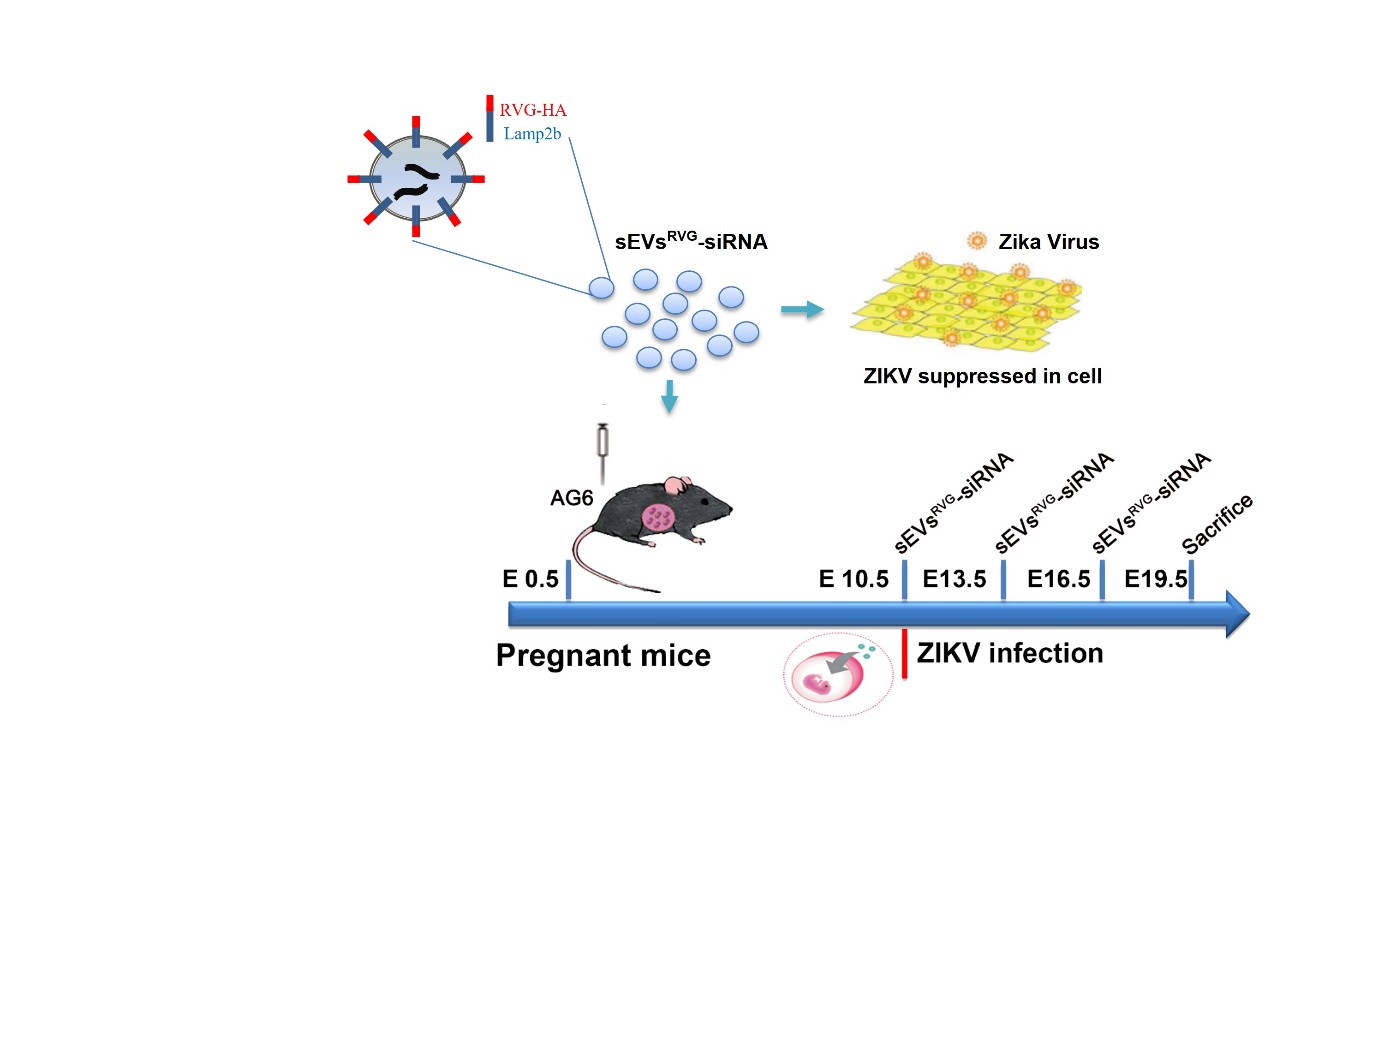

图1:研究工作示意图

为了开发一种能够穿越胎盘和血脑屏障的特异性抗病毒疗法来治疗ZIKV引起的小头症,我们设计了靶向脑部神经的细胞外小囊泡(sEVsRVG)并装载抗病毒siRNA(ZIKV特异性siRNA)来抑制ZIKV。细胞外小囊泡(sEVsRVG)的脑部神经特异性靶向是通过将sEVs膜蛋白lamp2b和神经靶向性的狂犬病毒糖蛋白衍生肽(RVG)融合递呈在细胞外囊泡上,在细胞及动物水平验证了sEVsRVG-siRNA的抗病毒能力

通过尾静脉给孕鼠注射sEVsRVG发现其能够穿透胎盘屏障及血脑屏障到达胎鼠脑部神经细胞,验证了sEVsRVG良好的组织穿透力及神经靶向性。

最后,研究人员通过用ZIKV感染怀孕AG6小鼠构建了胎鼠小头症模型,并在孕鼠攻毒0/3/6天后给予sEVsRVG-siRNA进行治疗,sEVsRVG-siRNA治疗组相对于其他组在孕鼠胎盘、子宫及胎鼠脑部有较为明显的抑制病毒作用;饲养胎鼠到一定天数后,对比发现治疗组胎鼠的小头畸形有明显缓解并且sEVsRVG-siRNA的治疗降低了病毒造成的神经损伤及炎症。 在未来,针对孕期病毒感染造成的胎儿脑部损伤,RVG修饰细胞外小囊泡装载抗病毒小分子靶向治疗或许是种潜在可能。该研究工作也引起了国外相关媒体的关注。